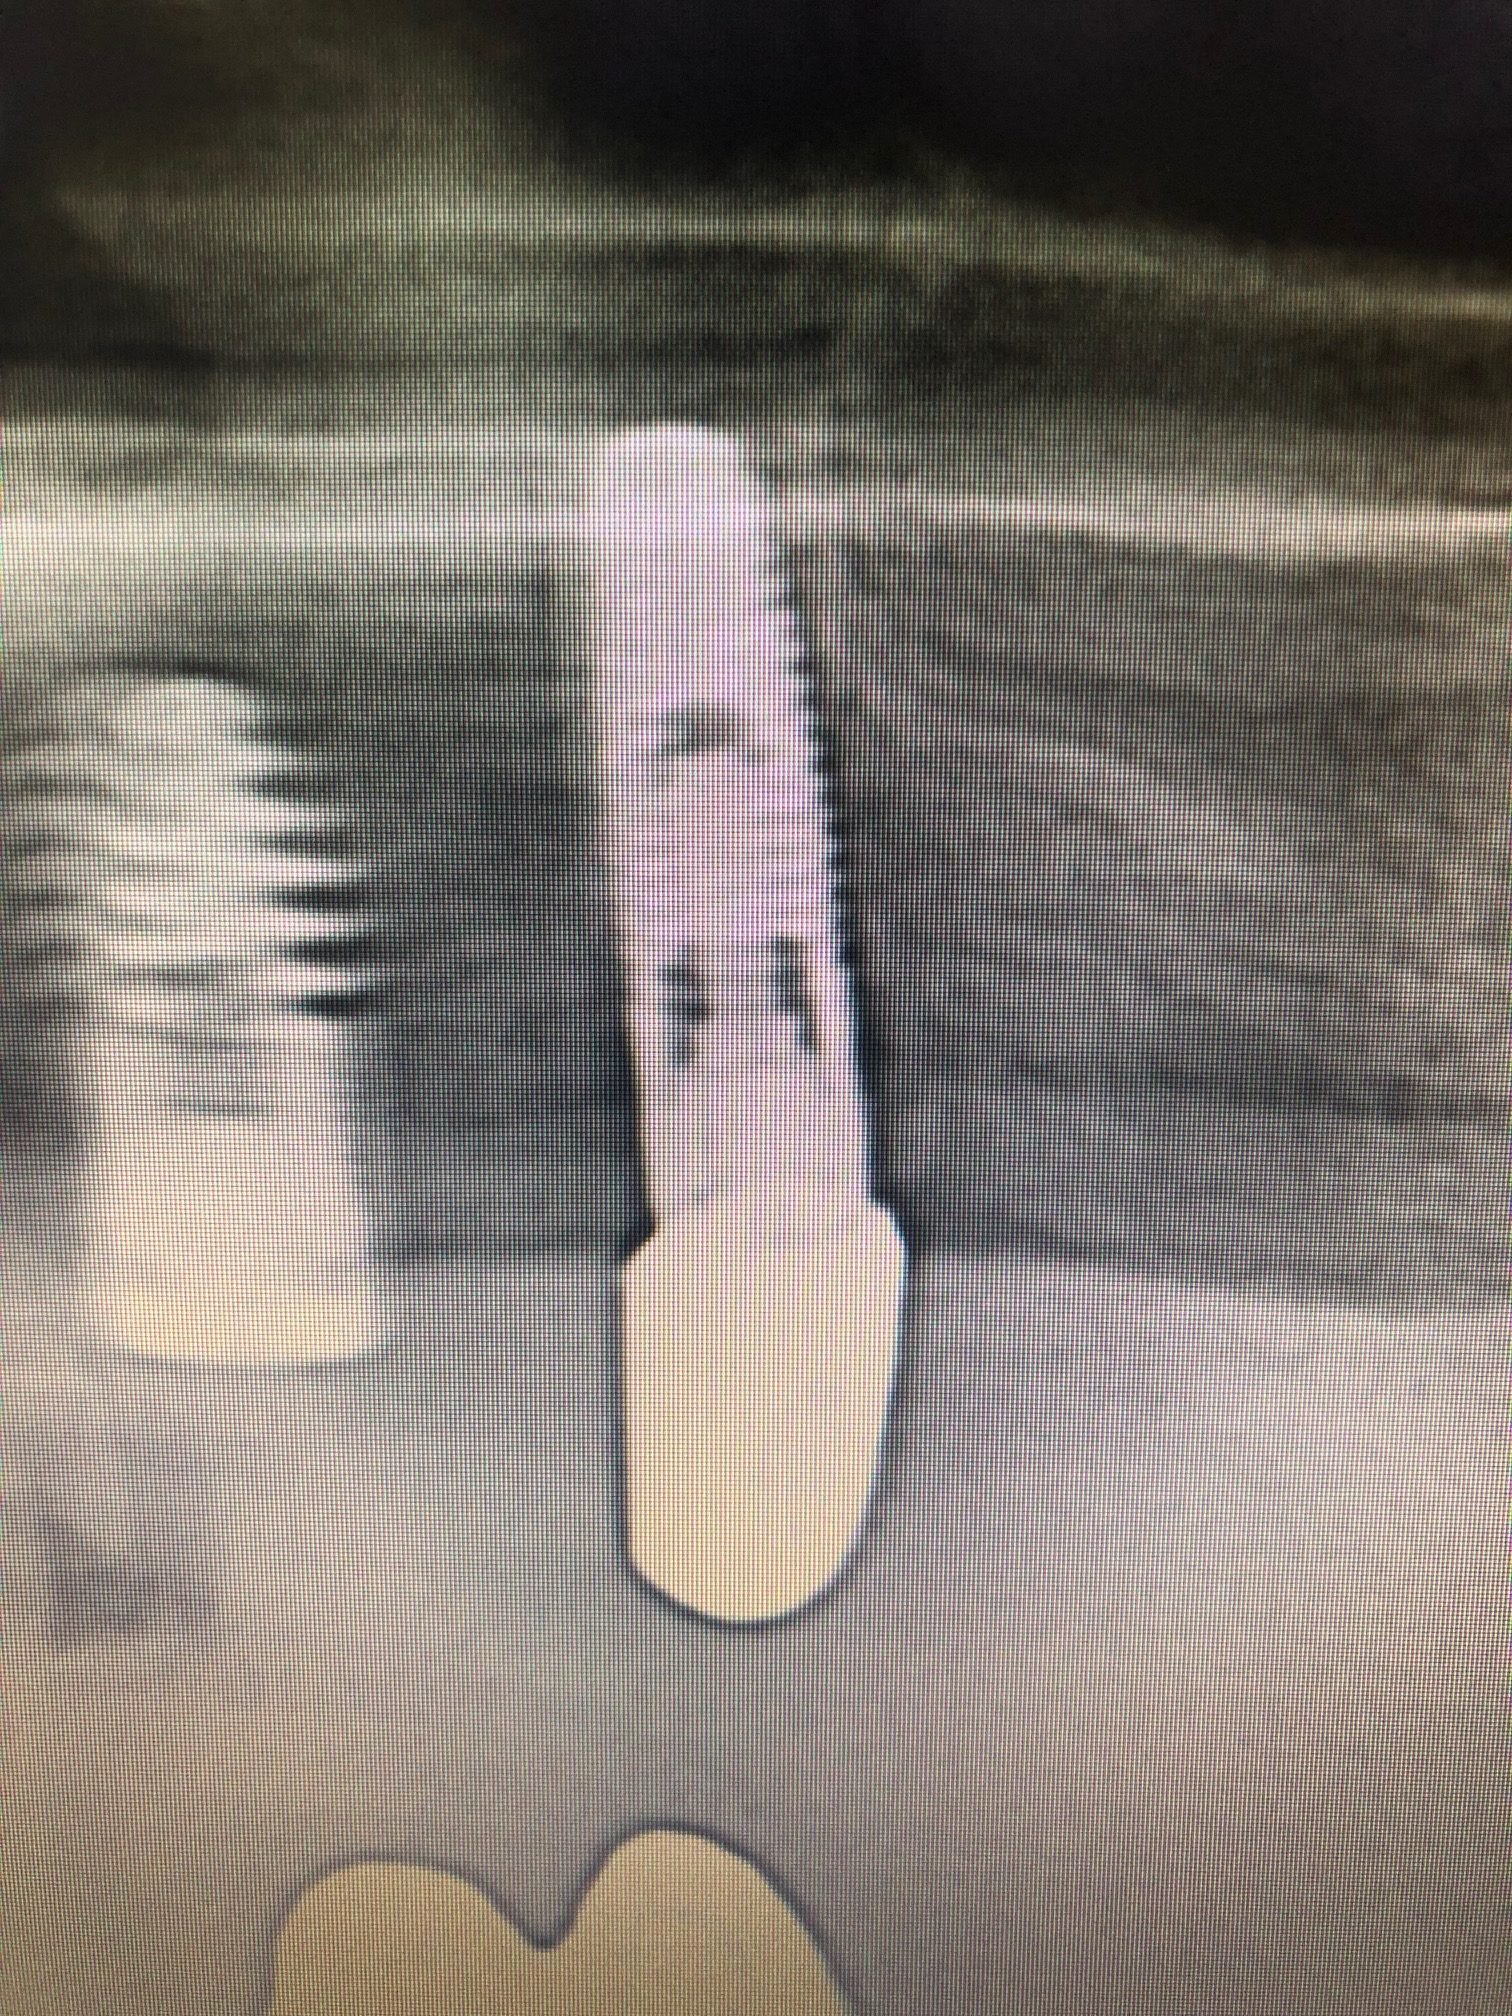

Buenas tardes! Este caso fue publicado recientemente en un foro de Facebook. Por petición del Dr. Valero, lo subo aquí. Paciente acude sin corona ni ningún tipo de pilar a [...]

Al paciente se le ha colocado un implante en 13 y se va a rehabilitar con ese implante que tiene en "16". El ultimo implante tiene un tornillo fracturado y [...]